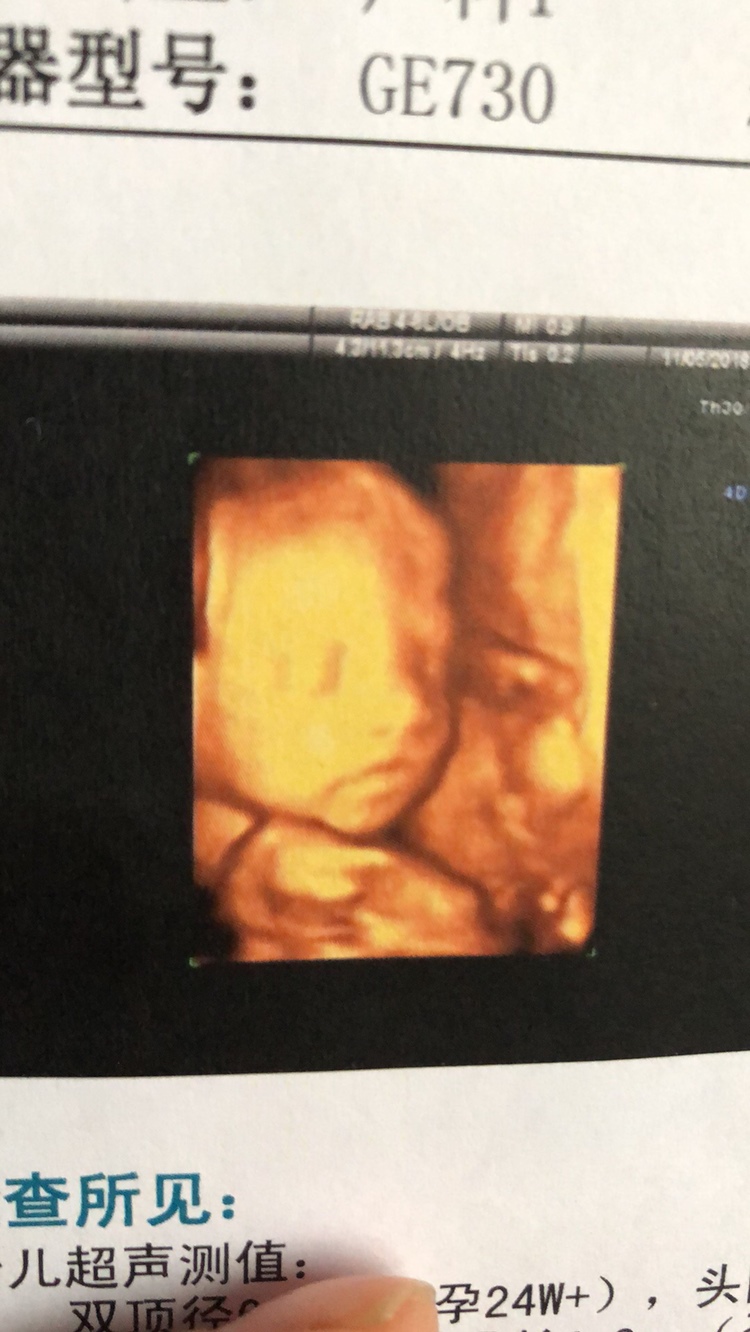

孕26周+4天